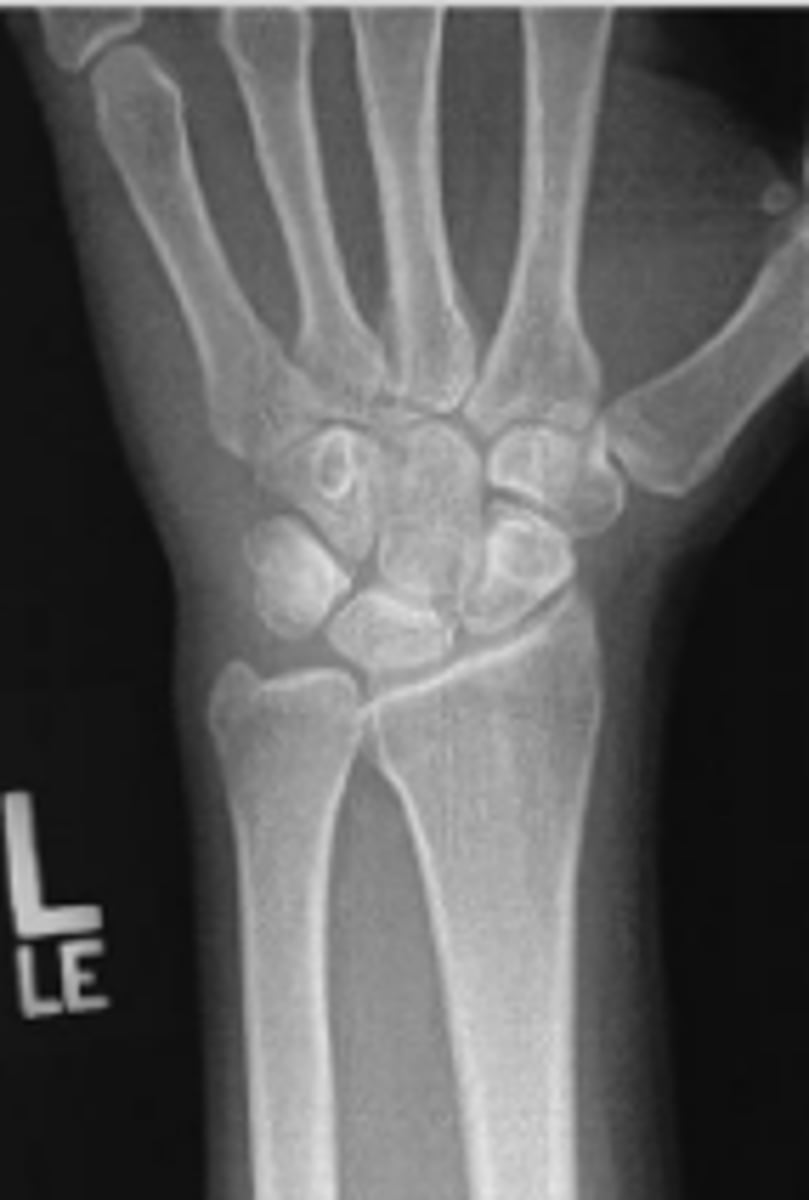

PA of the left wrist

What is the name of the radiographic view?